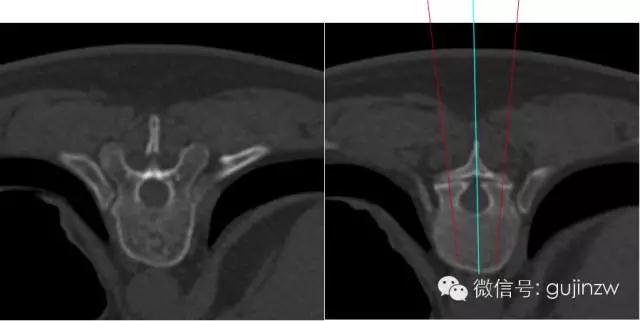

2、把握进钉水平面角度(TSA)和矢状面角(SSA):TSA角度可以从CT片子上测量,SSA与体位有一定关系,可以在术中用C型臂临控。

胸椎进针角度

矢状面:从T1到T2椎弓根内倾角度递减。T1 : 25°;T2 : 20 ° ; T3 :15° ; T4-9 : 10° ;T10: 5° ;T11-12:0° 。

- 上胸椎椎弓根螺钉应与矢状面呈10~20°的内倾夹角,中下段胸椎的椎弓根螺钉应与矢状面呈0~10°的内倾夹角。而Ebraheim提出T1、T2椎弓根螺钉应与矢状面呈30~40°内倾夹角,T3~T11呈20~25°,T12呈10°。

水平面:应与上下终板平行。